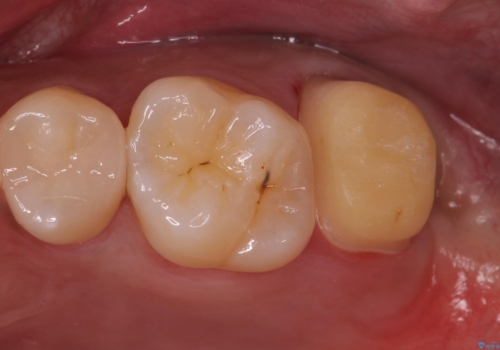

歯ぐきの形を整え、外れにくい被せ物を装着

歯のみでなく歯茎の調整も行うことで、外れにくい被せ物を装着することが可能になります。